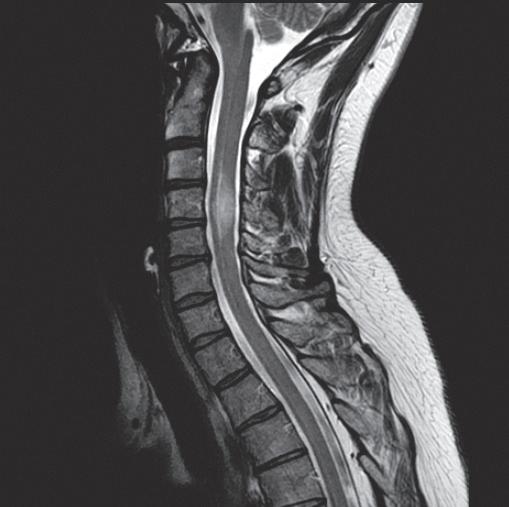

WHEN

WE OFFER

● Same- and next-day appointments with evening and weekend hours

● Subspecialized and DACBR radiologists who interpret patient exams and are available for consult

● Customized protocols:

● Weight-bearing imaging

● Flexion/extension imaging of the spine for a detailed diagnosis

● MRI options:

● 3T

● High-field open

● High-field wide-bore